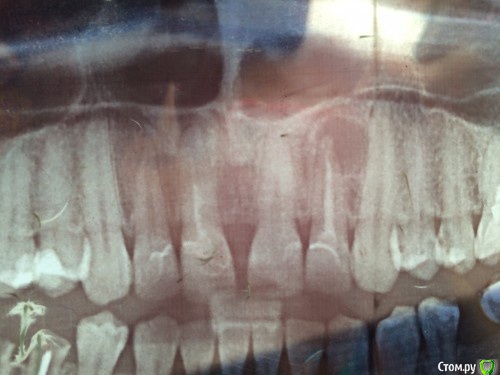

Кристина911 Опубликовано 23 июля, 2016 Поделиться Опубликовано 23 июля, 2016 Добрый день!В четверг мне лечили кисту 12 зуба, положили антибиотик и закрыли канал временной пломбой. Лечение проходила в институте челюстно-лицевой хирургии у кандидата наук, доктором очень довольна, после лечения боль сразу же ушла. Но через час-два появился небольшой отек (у крыльев носа со стороны больного зуба (12) который доходит почти до середины щеки, так же в этот же день поднялась температура до 37,7, сейчас температура спала, отек остается такой же и поверх него появилась краснота, так же присутствует головная боль и недомогание, легком надавливании на 12 и даже на 13 зуб появляется боль. Так же при надавливании на отек, он тоже болит. Вопрос мой таков, стоит ли срочно бежать к врачу или терпит до понедельника? Нормально ли мое состояние? Так же уточню, я на 8м месяце беременности. Институт сейчас не работает, а идти в первую попавшуюся клинику не хочу, может кто посоветует хорошего хирурга в Люберцах или Москве? Прилагаю снимок до лечения, чтобы видеть масштаб кисты. Ссылка на комментарий